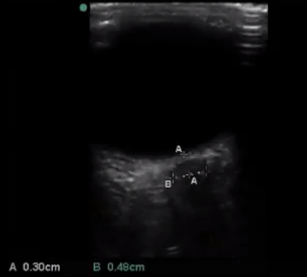

Ocular Optic Nerve Sheath Measure Image